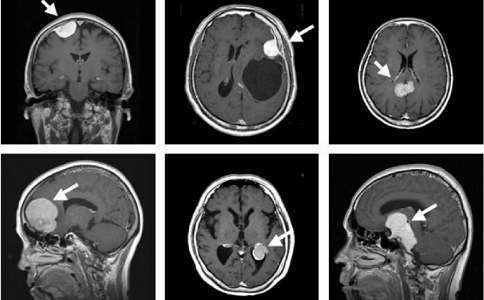

脑胶质瘤通常以手术治疗为主,但较难根治,易复发。一般手术的同时还要联合放疗、化疗、免疫治疗等治疗方法。想要获得有效的治疗,选择一家经验丰富的权威医院非常关键。那么治疗脑胶质瘤哪家医院好?接下来就请厚朴方舟的医学顾问老师来为大家盘点一下日本治疗脑胶质瘤的权威医院。